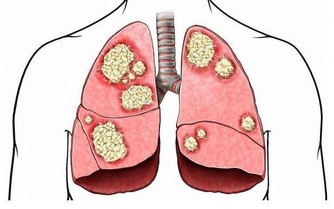

4. 誘發心臟病。牙垢久積所導致的牙周炎、牙髓炎會造成細菌毒素進入血液循環,最終危及心臟。

臨床上也顯示,經常患牙周炎、牙髓炎的人,患心臟病的幾率較常人高出許多。